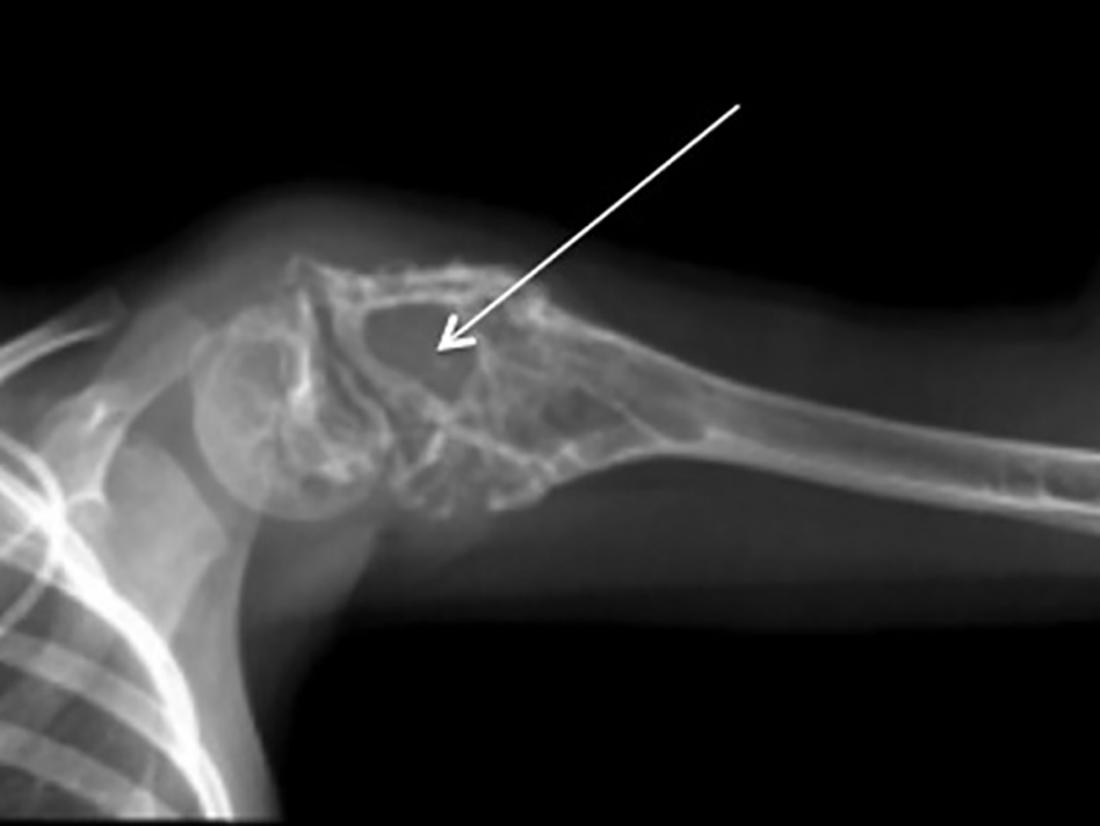

- X-ray: Uses energy beams to produce images of the inside of the body, including the area where the tumor is located.